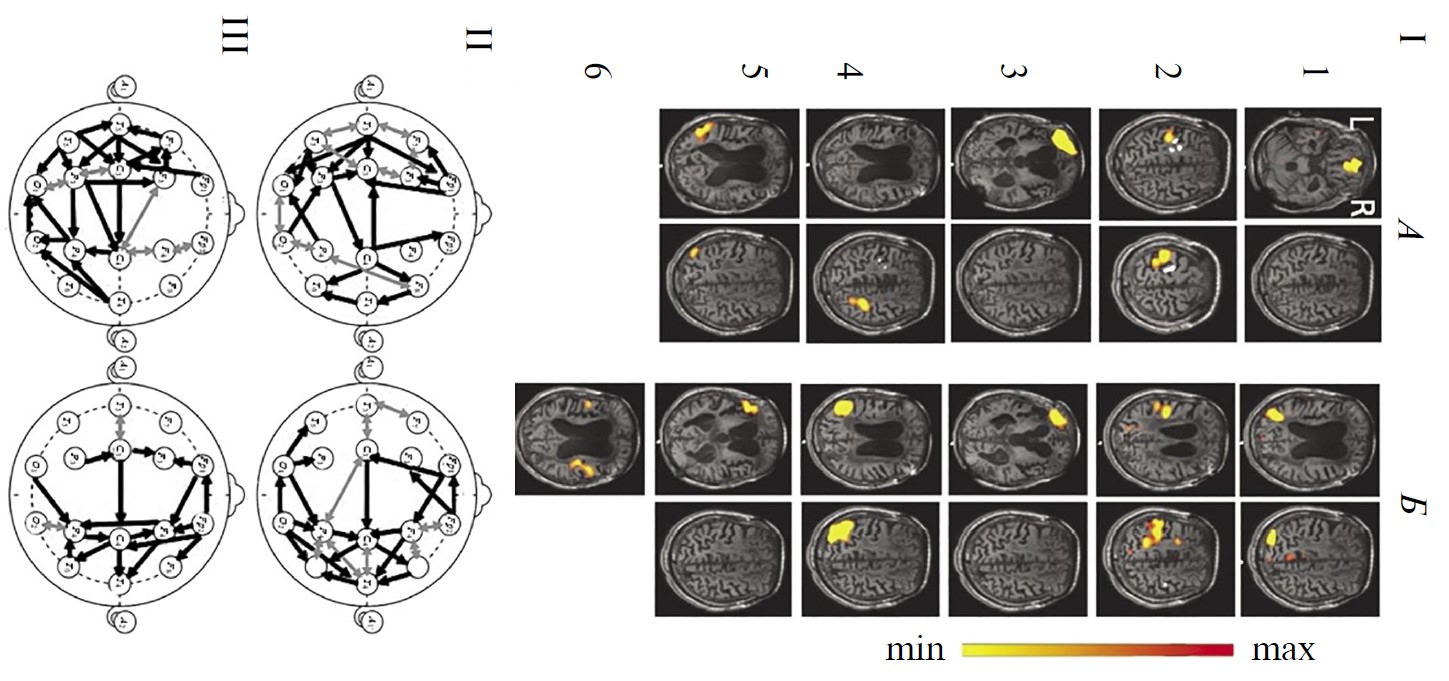

У здоровых испытуемых при групповом анализе RSN фМРТ были верифицировны все 6 сетей, указанных во введении в качестве наиболее значимых для восстановления сознания (рис. 1, А). Большинство из них (за исключением лобно-теменных) имеют симметричную билатеральную топографию, отражая наличие устойчивых межполушарных структурно-функциональных взаимодействий. В трех сетях (DMN, лобно-теменная, речевая) фокусы активности представлены как в лобных, так и в теменных (задне-височных) областях в пределах одного полушария, указывая на сохранность функционирования лобно-теменного пространства, необходимого для сознательной деятельности [1, 51, 52].

Рис. 1. Функциональные сети функциональной магнитно-резонансной томографии (фМРТ) и коннективность ЭЭГ-диапазона 1–15 Гц у здоровых испытуемых в состоянии покоя (n = 15).

А — усредненные по группе испытуемых RSN фМРТ: 1 – DMN, 2 - сенсомоторная, 3 – сеть управляющих функций (исполнительного контроля), 4 – лобно-теменная, 5 – слуховая, 6 – речевая. Шкала справа характеризует уровень максимальной интенсивности сети. Б, В — усредненная в этой же группе испытуемых коннективность ЭЭГ по корреляции Пирсона. Черные линии — однонаправленные связи, серые — двунаправленные, согласно методу причинности Грейнджера. Б — коннективности, рассчитанные на непрерывных записях, В — в режиме псевдо-ВП. Г — зоны концентрации функциональных связей ЭЭГ: а — лобные, б — височно-передневисочные, в — центральные, г — затылочно-теменные.

На рис. 1 представлены также результаты групповой оценки коннективности ЭЭГ диапазона 1–15 Гц этих испытуемых: при непрерывной записи состояния покоя (рис. 1, Б) и в режиме псевдо-ВП (рис. 1, В). На обеих схемах видно значительное число внутри- и особенно межполушарных связей, превышающих уровень корреляции Пирсона 0.5. Многие из них являются разнонаправленными (согласно методу причинности Грейнджера). Важно подчеркнуть, что паттерны связей характеризуются выраженным сходством друг с другом при обоих методах расчета коннективности. Хотя число отобранных связей несущественно меньше при расчете в режиме псевдо-ВП: 33 и 29 соответственно. Особенностью непрерывных записей ЭЭГ является также более частая встречаемость (на 7) двунаправленных связей.

Общее количество коннективностей ЭЭГ преобладает в передних корковых областях. В характере внутриполушарных связей, в первую очередь для непрерывных реализаций ЭЭГ (рис. 1, Б), можно отметить преимущественную правостороннюю направленность (по Грэйджеру) и превалирование их числа в правом полушарии, что, согласно литературным данным может рассматриваться как отражение возможно большей сопряженности этой гемисферы с ощущением своего тела [53] и самоосознанием [54].

Выделить на рис. 1 на схемах Б и В локусы топографического соответствия отдельным сетям фМРТ покоя затруднительно. Однако можно отметить несколько корковых областей, характеризующихся концентрацией функциональных связей: симметричные лобные, центральные, затылочно-теменные, а также височно-передневисочные. Топография этих локусов коннективности ЭЭГ (рис. 1, Г) совпадает с активными зонами сразу нескольких сетей фМРТ покоя: DMN, сенсомоторной, управляющих функций, слуховой и речевой. Можно полагать, что указанные области концентрации связей ЭЭГ можно рассматривать в качестве зон межсетевой коннективности, наличие которой отмечено в ряде публикаций в качестве значимой для восстановления сознания [43, 55].